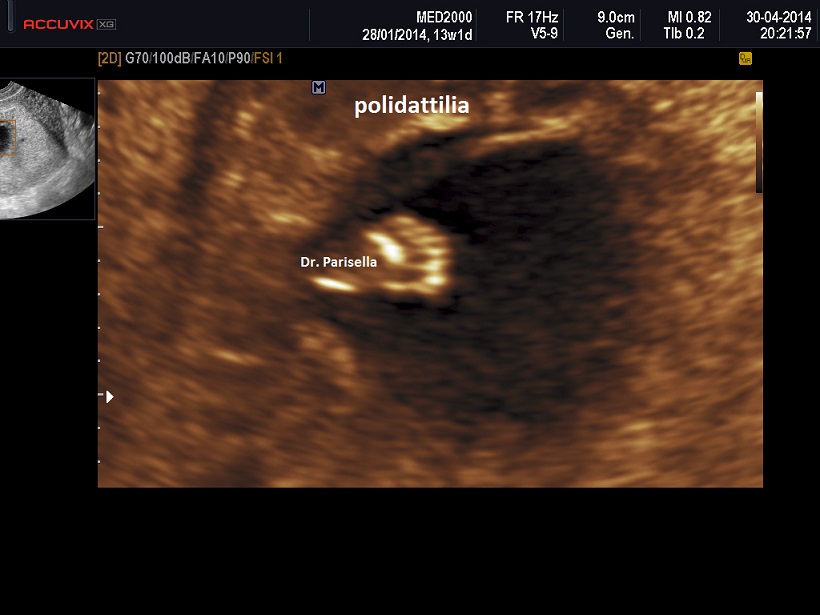

Meno frequentemente è presente polidattilia postassiale; se e’ presente coinvolge mani e piedi.